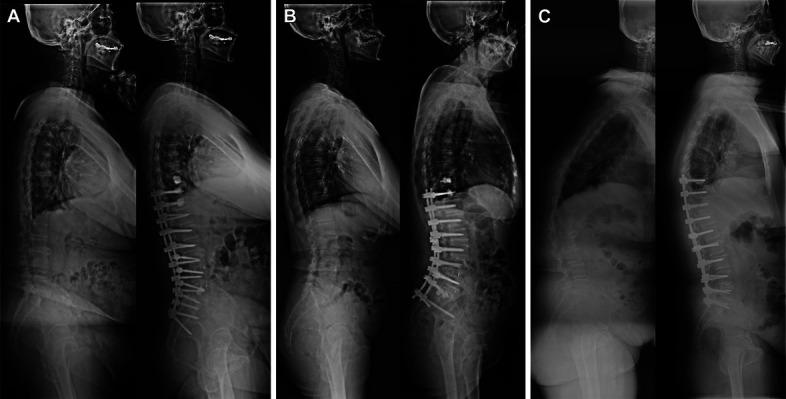

The Scoliosis Research Society (SRS)-Schwab system does not include a pelvic compensation (PC) subtype, potentially contributing to gaps in clinical characteristics and treatment strategy for deformity correction. It also remains uncertain as to whether PC has differing roles in sagittal balance (SB) or imbalance (SI) status. To compare radiological parameters and SRS-22r domains between patients with failed pelvic compensation (FPC) and successful pelvic compensation (SPC) based on preoperative SB and SI.

A total of 145 adult spinal deformity patients who received deformity correction were analyzed. Radiographic and clinical outcomes were collected for statistical analysis. Patients were classified into 4 groups based on the median value of PT/PI ratio (PTr) and the cutoff value of SB. Patients with low PTr and high PTr were defined as FPC and SPC, respectively. Radiographic and clinical characteristics of different groups were compared.

Patients with SPC exhibited significantly greater improvements in lumbar lordosis, pelvic tilt, PTr, and T1 pelvic angle as compared to patients with FPC, irrespective of SB or SI. No apparent differences in any of SRS-22r domains were observed at follow-up when comparing the SB-FPC and SB-SPC patients. However, patients with SI-SPC exhibited significantly better function, self-image, satisfaction, and subtotal domains at follow-up relative to those with SI-FPC. When SI-FPC and SI-SPC patients were subdivided further based on the degree of PI-LL by adjusting for age, the postoperative function and self-image domains were significantly better in the group with overcorrection of PI-LL than undercorrection of PI-LL in SI-FPC patients. However, no differences in these SRS-22r scores were observed when comparing the subgroups in SI-SPC patients.

Flexible pelvic rotation is associated with benefits to the correction of sagittal parameters, irrespective of preoperative SB or SI status. However, PC is only significantly associated with clinical outcomes under SI. Patients with SI-FPC exhibit poorer postoperative clinical outcomes, which should be recommended to minimize PI-LL.